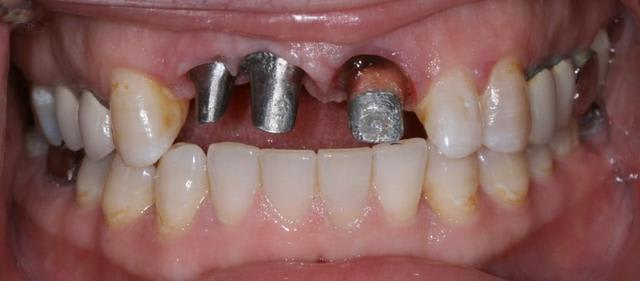

Bon ben j'ai implanté avant d'avoir refait la 21. Du coup j'ai mésialé la pose de 11 pour compenser la distalisation de 21.

Au final je n'ai pas fait de greffe osseuse... et j'ai réalisé une technique de rouleau sur 11-12 mais je reste un peu court à mon goût.

J'ai mis en place des transitoires sur 11-12-21 pour temporiser 3 mois pour voir la maturation des tissus mous.

Je réaliserai dans un second temps des piliers procera.

Je mets quelques photos de la patiente au cab et du prothèsiste d'Epinal.

La vraie difficulté a été de retrouver le milieu incisif pour déterminer la position des implants.

tu as mis des piliers provisoires que j'aime pas bcp, comment tu fais avec les gaines ?

Elles sont adhérente aux la provisoires ? Tu scelles ? Perso je préfère transviser, c'est moins galère

Les provisoires sont solidaires ? ( bravo pour le parallélisme)

Le zénith de la 21 doit être un peu plus distal pour que le résultat soit plus sympa

(comme tu l'as si bien fit sur la 11, allez quoi, un petit coup de bistouri et hop tu gagnes en esthétique)